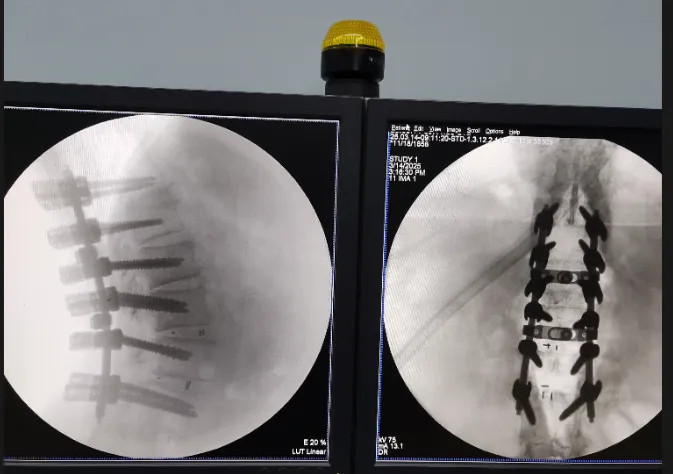

3月14日,在Stryker公司特別調(diào)撥的初代Opus專用工具護航下,林翔團隊歷時6小時完成胸椎管擴大減壓+腰椎翻修+脊柱矯形三大術(shù)式整合。當看到患者術(shù)后即刻恢復足部活動時,整個醫(yī)護團隊都露出了欣慰笑容。

(術(shù)中C臂透視下精準操作場景)

(術(shù)后透視)